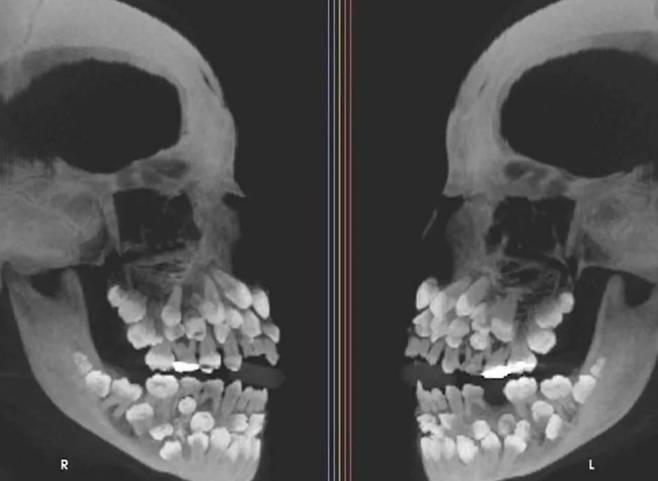

브라질의 11세 소녀가 유치를 뽑으러 갔다가 입안에 수십 개의 치아가 숨어있다는 사실을 알아냈다.

소녀의 치아는 총 81개로 세계적으로 드문 사례다.

15일(현지시간) VN익스프레스 등 외신에 따르면, 브라질 미나스제라이스주에 사는 소녀는 유치를 뽑기 위해 치과를 찾았다가 엑스레이 사진을 보고 충격 받았다. 아직 나지 않은 치아를 포함해 모두 81개가 있었기 때문이다.

일반적인 성인의 치아 수는 28개이며 사랑니를 포함하면 32개다.

그런데 이 소녀는 유치 18개에 영구치 32개, 과잉치가 31개였다.

소녀를 진료한 병원 연구진은 “이런 상태는 ‘다발성 과잉치증’”이라며 “과잉치는 보통 한두 개 생기는데, 30개가 넘는 경우는 거의 없다”고 설명했다.